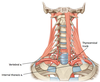

What are the borders of the ANTERIOR triangle?

(medial, lateral, superior)

Medial = Midline of neck

Lateral = Anterior border of sternocleidomastoid

Superior = Inferior border of mandible

What are the 4 blood vessels found in the ANTERIOR trinagle?

(4)

Common carotid a.

External carotid a.

Internal carotid a.

Internal jugular v. + tributaries